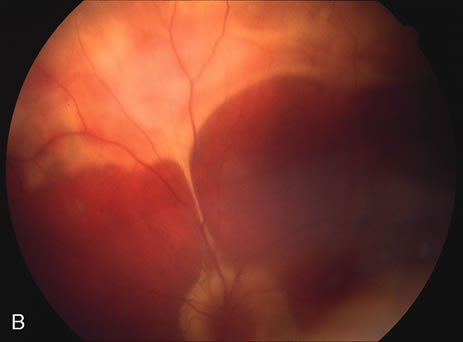

RETINAL FINDINGS

The fundus findings tend to depend on the chronicity of the disease. In new-onset cases, there are just a few choroidal lesions most of which are in the posterior pole. The newer lesions tend to be yellowish-white in coloration and with time they become punched-out. The size of the lesions can be variable ranging from one third to 1 disc diameter in size. They can become confluent and so they may appear larger than the typical size. The newer lesions are associated with visual distortions. Rarely subretinal fluid may be present over fresh choroidal lesions. In addition, choroidal neovascularization may be seen in one third of cases. Subretinal hemorrhage and subretinal fluid should be considered as signs of the development of a possible choroidal neovascular membrane. Retinal phlebitis is rarely present but may be seen as well (Fig. 9).

Fig. 9. A and B. Fundus photographs of the right and left eye showing the classic circular choroidal lesions with marked pigment clumping in a case of multifocal choroiditis.